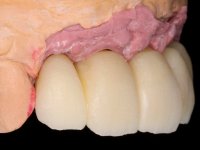

O paciente foi observado conjuntamente e a dúvida que surgiu de imediato foi se seria possível com a regeneração óssea a efectuar poder ser reabilitada naturalmente a zona das papilas interdentárias. Nesse sentido foi feito um enceramento de diagnóstico que contemplaria as duas hipóteses, utilizando ou não a cerâmica gengival. A confecção desse enceramento foi fundamental para expor ao paciente a dificuldade da reabilitação. O wax-up deu origem a um mock-up que foi aprovado pelo paciente e que simultaneamente serviu de guia imagiológica. O caso foi planificado cirurgicamente e realizada uma guia cirúrgica com que foram colocados os implantes. Após 10 semanas foi feita a 1ª impressão para confecção da ponte provisória. Foram criados os primeiros perfis de emergência na gengiva artificial e foi digitalizado o modelo. Por processo de CAD-CAM foi confeccionada uma ponte provisória aparafusada baseada no enceramento de diagnóstico. A ponte trabalhou durante 8 semanas os tecidos moles que foram fielmente copiados numa impressão com técnica de moldeira aberta. Os transferes foram individualizados com resina composta para copiarem fielmente os perfis de emergência criados pela ponte provisória. Confeccionado o modelo de trabalho definitivo, foi realizada uma infra-estrutura em zircónio seguindo a orientação do enceramento de diagnóstico. O assentamento da infra-estrutura foi testado em boca e simultaneamente foi novamente impressionados os tecidos moles com um silicone fluido. Nessa consulta foi feito o levantamento da cor. Os dentes 13 e 23 apresentavam uma saturação anormalmente forte que resolvemos não valorizar, optando por privilegiar a relação com o sector antero-inferior. Foi realizada uma nova gengiva artificial com a impressão que acompanhou a impressão de arrasto com a infra-estrutura. Após a colocação da cerâmica na infra-estrutura foram coladas as meso-estruturas. O trabalho final foi aparafusado lentamente permitindo a adaptação dos tecidos moles.